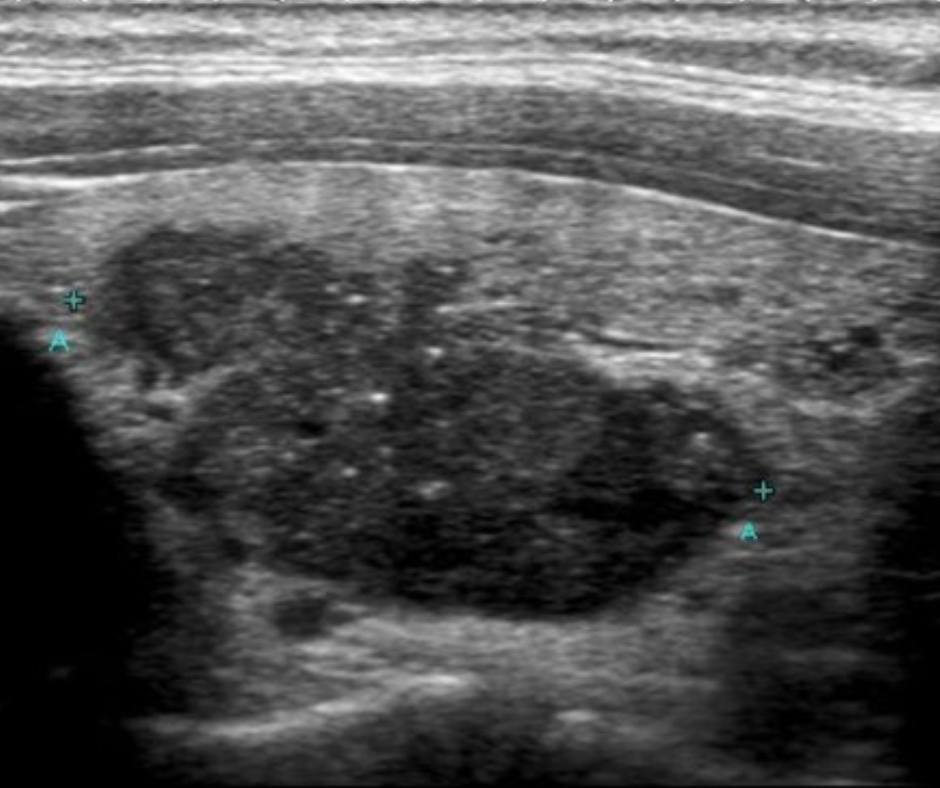

Figure 1: Ultrasound image of a cancerous thyroid nodule

Figures 2-4: Ultrasound images of multiple enlarged, cancerous lymph nodes with a speckled, irregular appearance in the left side of the neck.